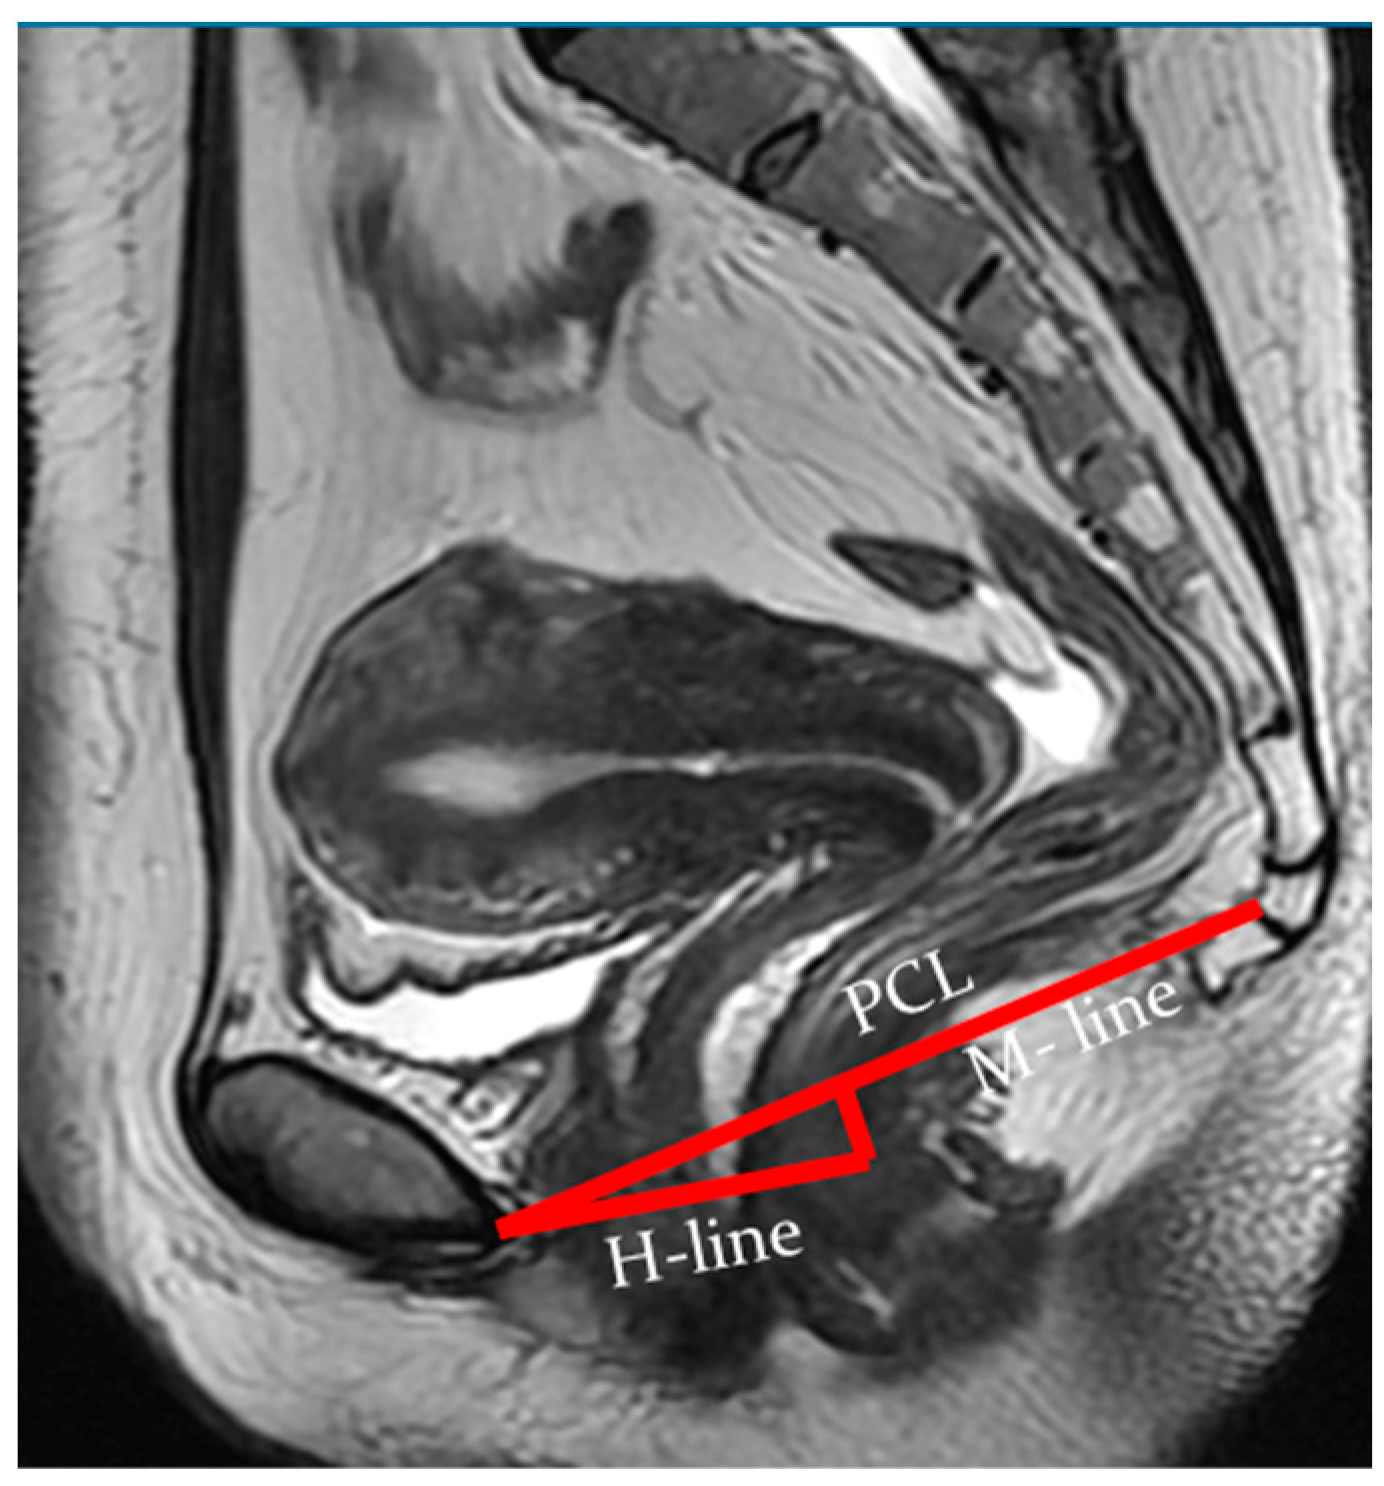

Indicators of the condition of the pelvic organs are assessed in relation to the PCL, connecting the lower edge of the pubic symphysis with the last coccygeal junction; the H line—the line connecting the lower edge of the pubic symphysis with the posterior wall of the anorectal junction, which corresponds to the urogenital slit, and its sagittal size must not exceed 5 cm; and the M line—the perpendicular connecting the H line with the PCL, which must not exceed 2 cm (Figure 3).

At rest, the bladder floor is located 2 cm above the PCL. The urethral axis is vertical at rest and may shift slightly when pushing, and the urethral lumen does not gape. At rest, the cervix is 4 cm above the PCL. When pushed, the cervix is 8 mm above the PCL with the H and M lines lengthening slightly while pushed (Figure 4 and Figure 5).

According to dMRI data, regardless of prolapse status, women with levator defects have a lower pelvic organ location due to a widening of the urogenital slit [41]. H and M lines are used to estimate the size of the urogenital crevice on MRI. The H line is a representation of the anteroposterior dimension of the urogenital crevice and is usually <6 cm in length; an increase in this distance indicates a widening of the urogenital crevice, which may be the cause of pelvic organ prolapse. An increase in the H line to 6–8 cm is regarded as a mild degree of widening of the urogenital crevice, 8–10 cm is a medium degree of widening, and more than 10 cm is a severe degree.

The M line, which is the vertical distance from the PCL to the H line at the level of the anorectal junction, is usually <2 cm in size. An increase in the M line to 2–4 mm is a sign of mild posterior compartmental prolapse, 4–6 cm is a moderate degree, and more than 6 cm is a severe prolapse [41].

Figure 3. Assessment of pelvic organ parameters in relation to PCL and H and M lines.